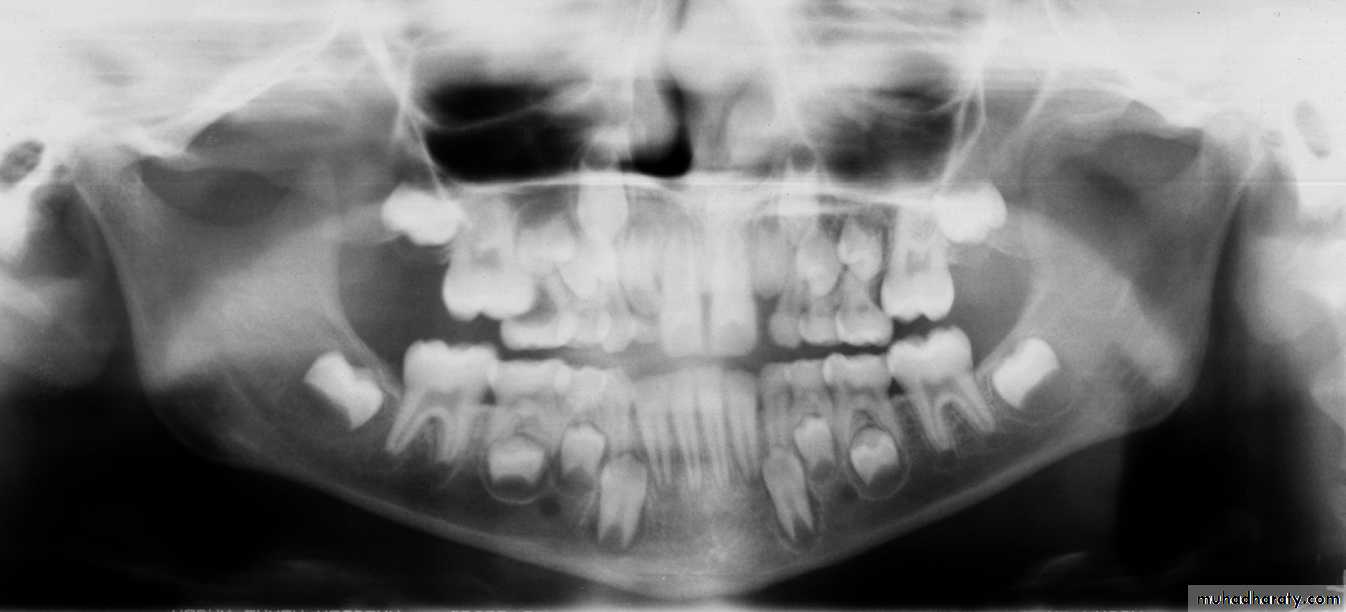

Panoramic is recommended at approximately the time of the early mixed dentition to assess

1. the dental age of the patient and

2. to aid in the early diagnosis of congenital and developmental anomalies.Panoramic radiograph

Patient’ age nearly 9 because the lower canines erupted and their eruption on 9-10 year and the upper lateral emerging now

This child is 7-8 years old because he has the upper maxillar centrals erupted (depending on schedule of time of eruption of permanent teeth (eruption lecture)